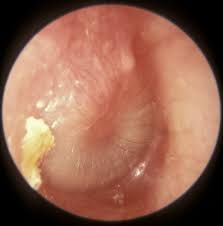

Otitis Media with Effusion

Tympanic membrane is retracted with prominence of handle of malleus which is more horizontal

Tympanic membrane may be bulging or have air fluid level behind

Yellow/amber appearance

Light reflex apparent